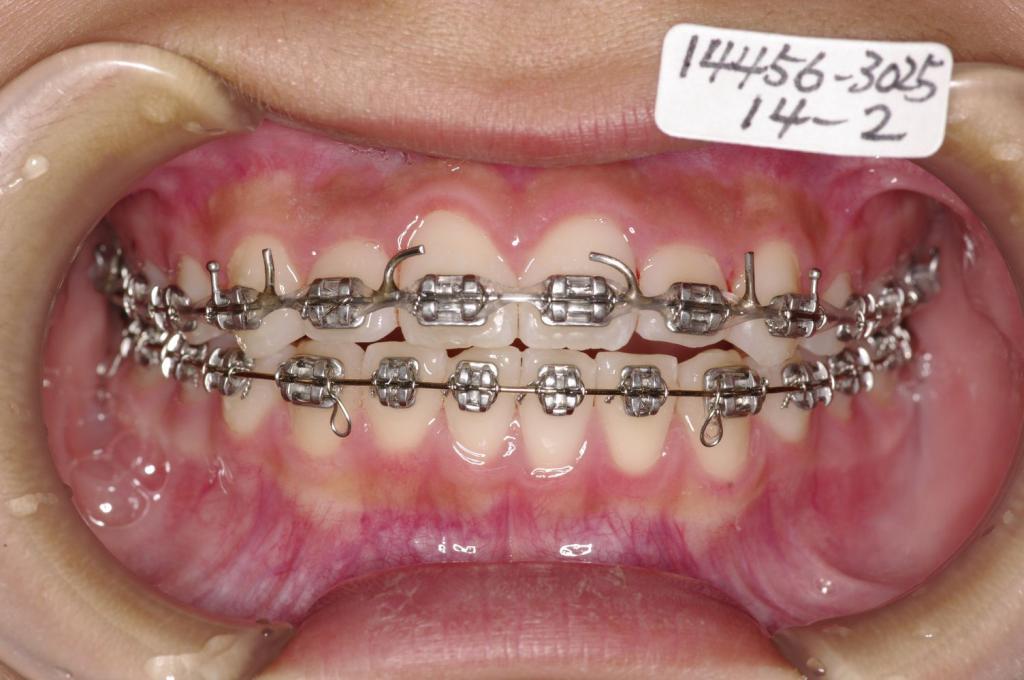

装置の種類及び治療法 診断:叢生

治療方法および装置:マルチブラケット装置

High pull J-hook headgear

抜歯:非抜歯

装置写真

歯並び・咬み合わせ・八重歯・乱杭歯の矯正治療前口内写真NO.1199

歯並び・咬み合わせ・八重歯・乱杭歯の矯正治療後口内写真NO.1199